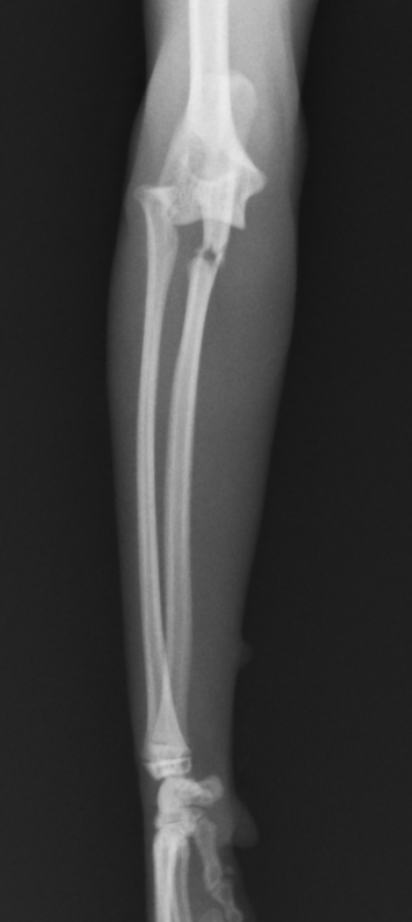

今回の症例はキャットタワーから落下して足を上げてしまうとのことで来院しました。尺骨の近位が骨折し、橈骨が外側に変位してしまっています。診断はモンテジア骨折Ⅲ型でした。全く足をつくことができないため、手術が必要と判断し行いました。

正面から撮影したX線の拡大です。紫が尺骨の骨折で、緑が、脱臼した橈骨になります。

横から撮影したX線の拡大です。左が正常の骨で、右が骨折した骨です。

青丸が尺骨の骨折、緑丸が橈骨頭の脱臼です。